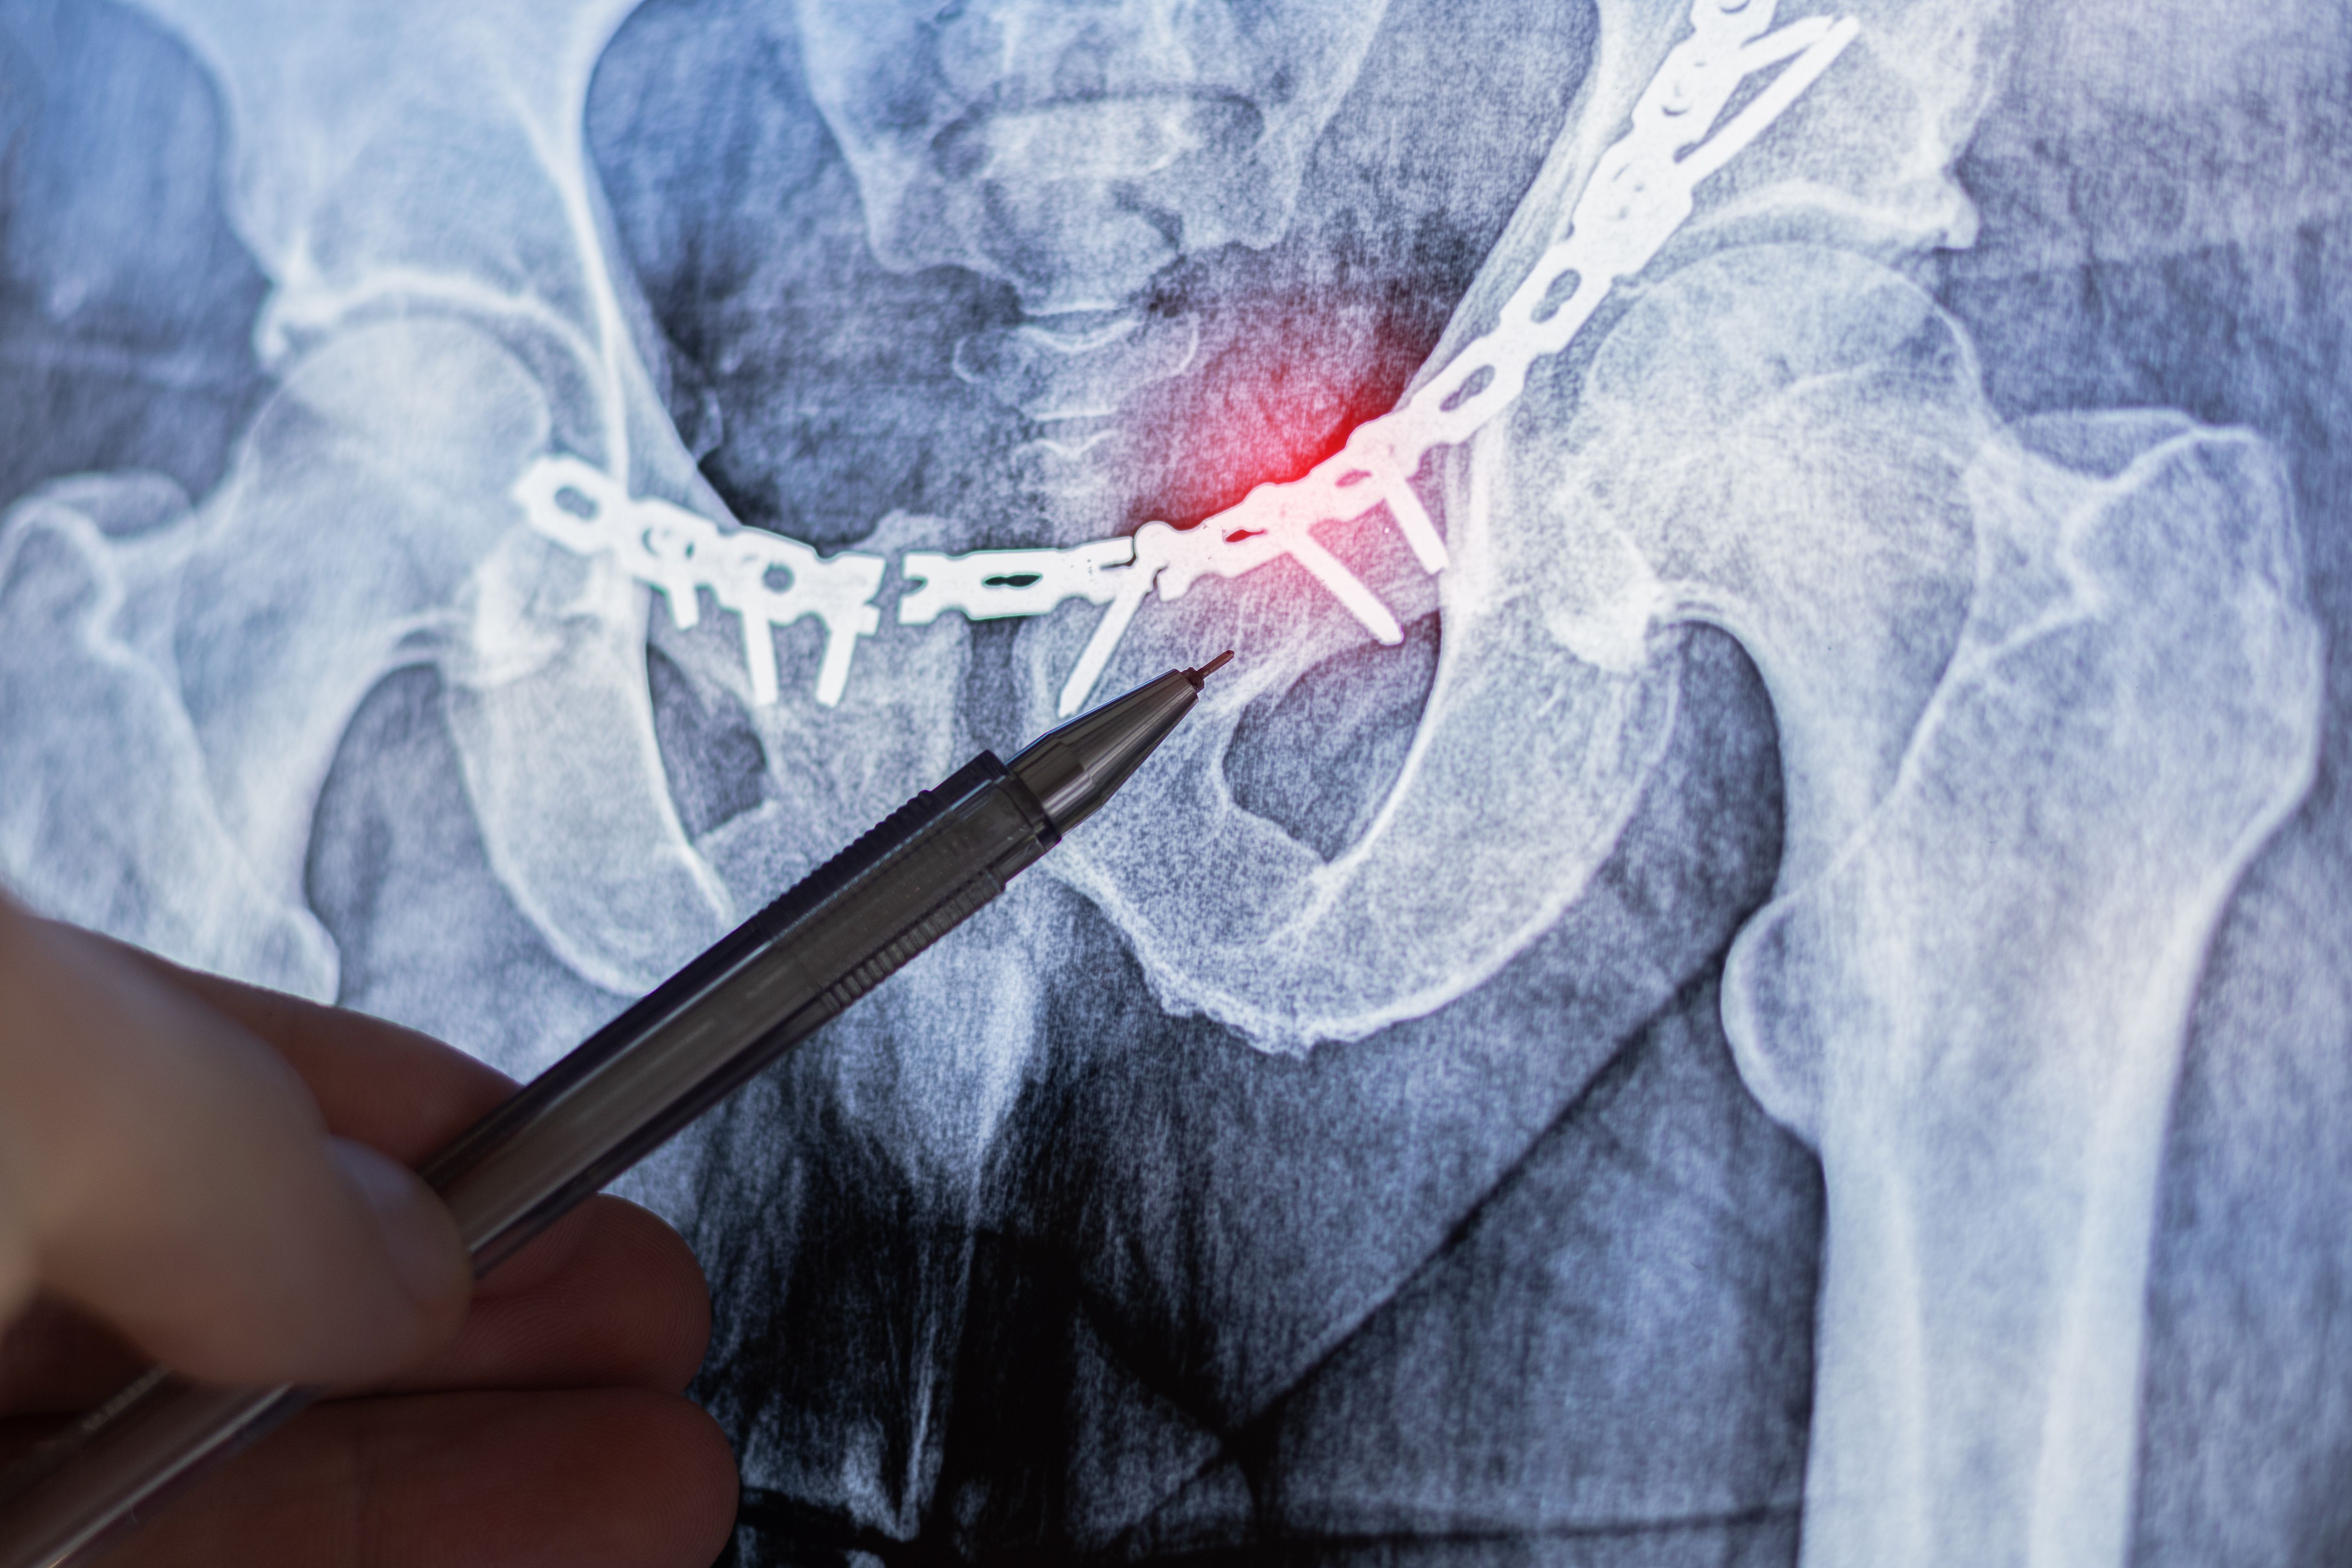

Innovationen in der Implantattechnologie

Eine der bedeutendsten Entwicklungen in der Orthopädie ist der Fortschritt in der Implantattechnologie. Neue Materialien und Designverbesserungen machen Implantate haltbarer und verträglicher für den menschlichen Körper. Patienten profitieren von einer längeren Haltbarkeit und geringeren Komplikationen nach der Operation.

Besonders hervorzuheben sind die Fortschritte bei personalisierten Implantaten, die mit Hilfe von 3D-Drucktechnologie hergestellt werden. Diese maßgeschneiderten Lösungen sorgen für eine bessere Passform und reduzieren das Risiko von Abstoßungsreaktionen.